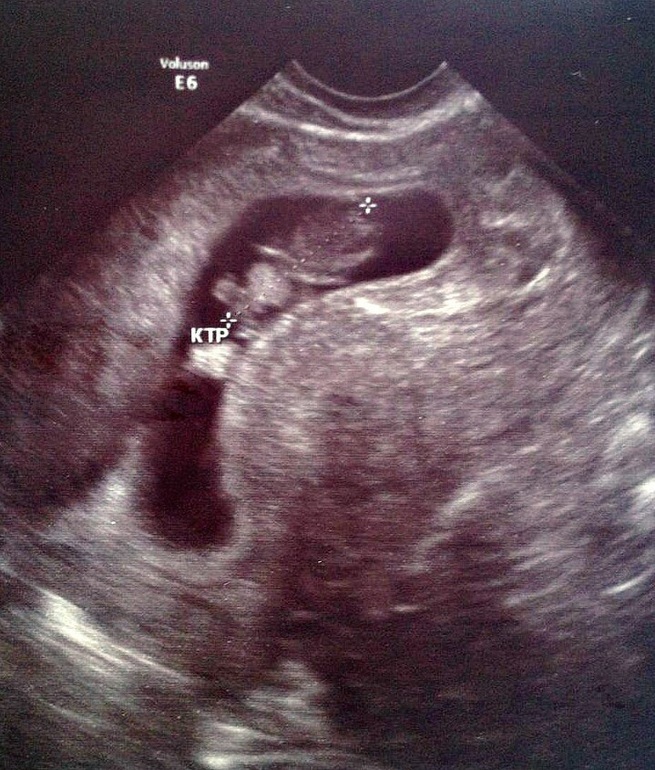

Вот ..как то так..

Дай бог мне такое же чудо?!! Вам удачно выносить желаю